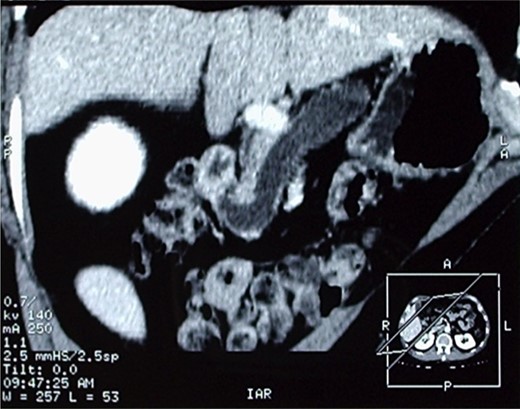

A Cholangio-magnetic resonance imaging (MRI) (Fig. 3) revealed that the sero-cystic lesion found at CT, was being mimicked by the enormously dilated pancreatic duct that had reached a diameter of 2 cm at the level of the pancreatic body. The dilation decreased to 1 cm in the pancreatic tail and the lumen of the Wirsung duct seemed to have an irregular profile. On the opposite side, the Wirsung caliber suddenly decreased in proximity to its duodenal end. This finding was not univocal and could suggest an intraductal mucous secreting tumor, chronic pancreatitis or an ampullary alteration. The pancreatic parenchyma of the body and of the tail was remarkably hypotrophic, and only some residual pancreatic tissue was observed at the uncinate process. The choledochus maintained a regular size almost down to its duodenal end, but in proximity of the Vater ampulla it disappeared for about one cm, suggesting a functional spasm or, more likely, a pathologic process of the ampulla. An octreoscan did not demonstrate any somatostatin receptor.

Cholangio-MRI, showing an enormously dilated pancreatic duct, with the diameter of 2 cm at the level of the pancreatic body mimicking the sero-cystic lesion found at CT.